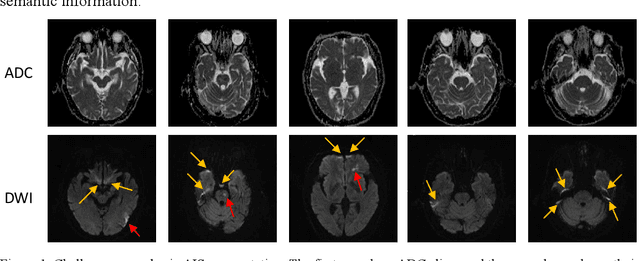

Abstract:Ischemic stroke is a common disease in the elderly population, which can cause long-term disability and even death. However, the time window for treatment of ischemic stroke in its acute stage is very short. To fast localize and quantitively evaluate the acute ischemic stroke (AIS) lesions, many deep-learning-based lesion segmentation methods have been proposed in the literature, where a deep convolutional neural network (CNN) was trained on hundreds of fully labeled subjects with accurate annotations of AIS lesions. Despite that high segmentation accuracy can be achieved, the accurate labels should be annotated by experienced clinicians, and it is therefore very time-consuming to obtain a large number of fully labeled subjects. In this paper, we propose a semi-supervised method to automatically segment AIS lesions in diffusion weighted images and apparent diffusion coefficient maps. By using a large number of weakly labeled subjects and a small number of fully labeled subjects, our proposed method is able to accurately detect and segment the AIS lesions. In particular, our proposed method consists of three parts: 1) a double-path classification net (DPC-Net) trained in a weakly-supervised way is used to detect the suspicious regions of AIS lesions; 2) a pixel-level K-Means clustering algorithm is used to identify the hyperintensive regions on the DWIs; and 3) a region-growing algorithm combines the outputs of the DPC-Net and the K-Means to obtain the final precise lesion segmentation. In our experiment, we use 460 weakly labeled subjects and 15 fully labeled subjects to train and fine-tune the proposed method. By evaluating on a clinical dataset with 150 fully labeled subjects, our proposed method achieves a mean dice coefficient of 0.639, and a lesion-wise F1 score of 0.799.